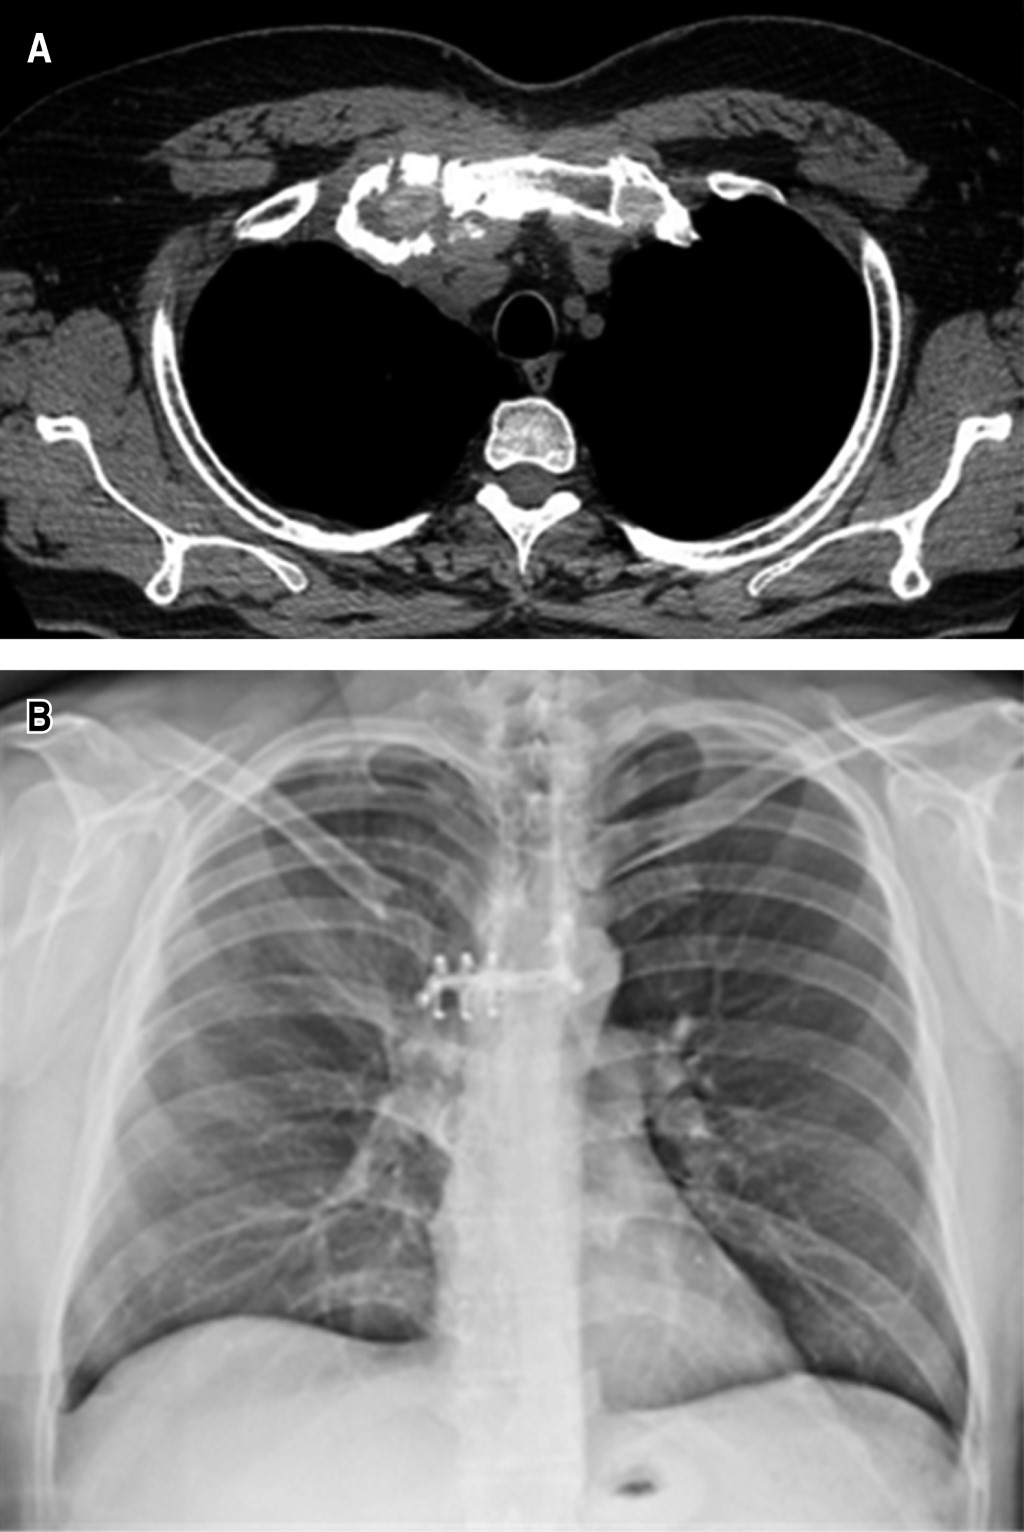

• ? Caso 1: masculino de 51 años de edad con tumor de articulación esternoclavicular y esternocostal derecha, el cual se resecó con bordes libres y se reconstruyó con sistema StraTos®, sistema Tritium® y malla parcialmente absorbible (Figura 1).

Figura 1